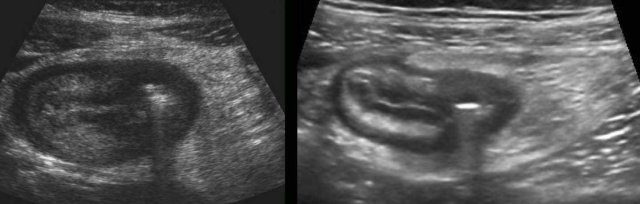

Skip lesions

One of the features of Crohn’s disease is the patchy way it affects bowel.

This results in skip lesions,  where large parts of the bowel are left unharmed.

The affected parts show a relatively sharp demarcation, the transition from normal (small arrows) to abnormal bowel (large arrows) being rather abrupt.